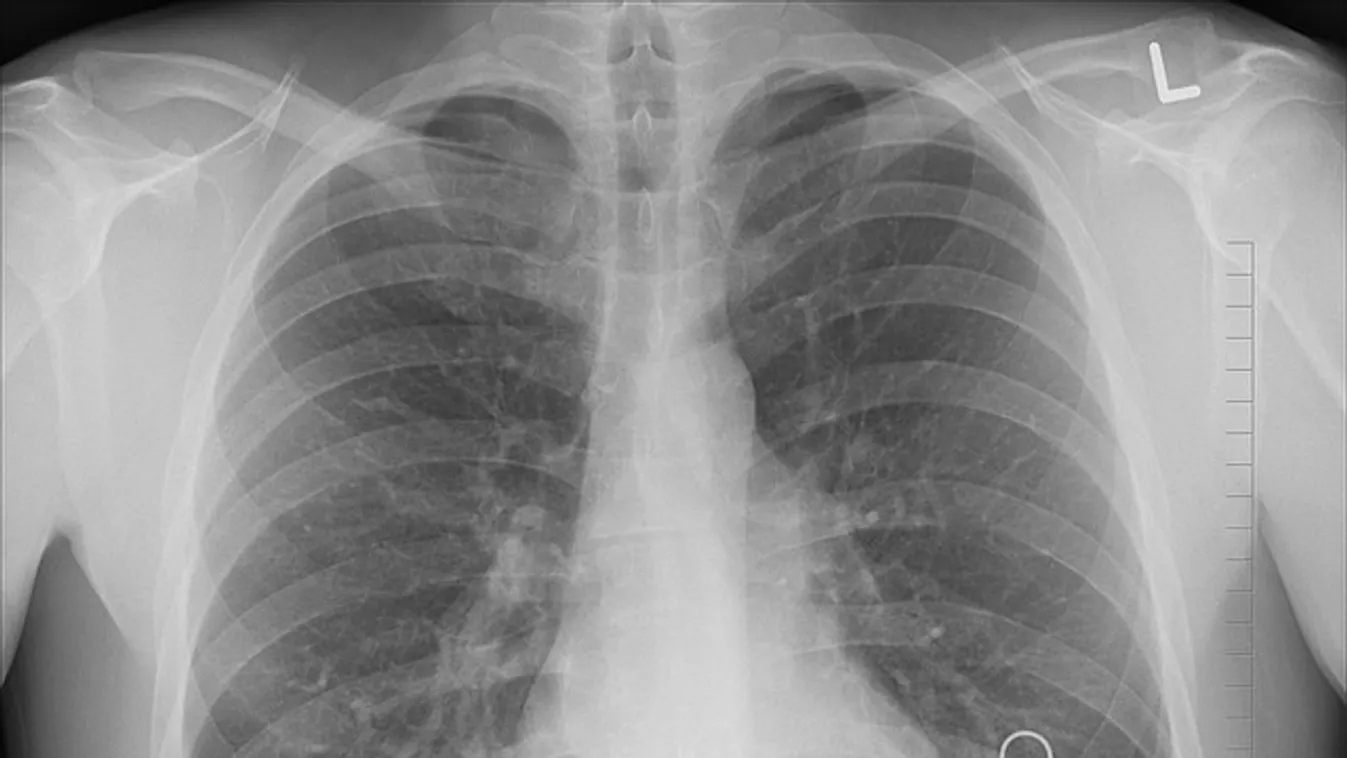

Jelentős a különbség az oltott és oltatlan betegek tüdőkárosodása tekintetében koronavírus-fertőzés esetén.

„A koronavírussal megfertőződött, de beoltott emberek több mint 95%-ának nem károsodik a tüdeje” – állítja a temesvári Victor Babeș Fertőző- és Pneumoftiziológiai Kórház orvos igazgatója, Diana Manolescu.

Állítását röntgenfelvételekkel támasztotta alá a szakember:

A koronavírussal kórházba került oltott és nem oltott személyek esetében a legnagyobb különbség a tüdő károsodásában vehető észre. Míg a beoltott emberek 95 százalékánál nincs tüdőkárosodás, addig az oltatlanok esetében a tüdő jelentősen károsodik.

„Az oltatlan betegeknél a tüdőkárosodás 30-40 százalékkal kezdődik, és rövid időn belül tovább romolhat, akár 70-80, sőt 85 százalékosra is” – mondta Diana Manolescu. „Sajnos ezek a tüdőelváltozások gyakran összeegyeztethetetlenek az élettel” – magyarázta. „Az egyetlen megoldás a védőoltás” – zárta a videót a doktornő.